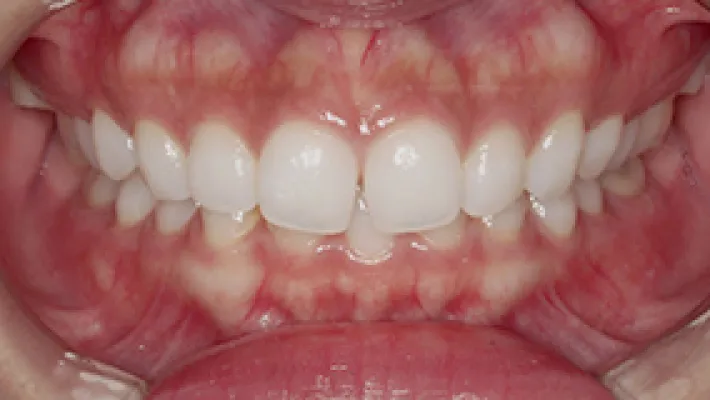

上下前歯すきっ歯 マウスピース矯正

施術前

施術後

マウスピース矯正の部分矯正で上下前歯のすきっ歯を改善した症例です。

状態にもよりますが、すきっ歯はマウスピース矯正の得意とするケースの一つです。

効率的な治療計画で最小限の期間と負担で矯正を行いました。

矯正治療の期間・方法

矯正治療の期間や方法は歯並びや顎骨などの状態によって大きく異なります。

矯正治療は歯や歯周組織などに必ずダメージがあります。

矯正治療のダメージを最小限にするために健康的で現実的な治療計画を提案します。

治療費

470,000

治療期間

6.5ヶ月